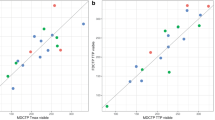

The CBF indices of BEANR and 123I-IMP SPECT were significantly and positively correlated (r = 0.55, p < 0.0001), but there was no significant correlation between the rSVD method and SPECT (r = 0.15, p > 0.05). BEANR produced smaller limits of agreement for CBF than rSVD. The mean difference in the CBF index between BEANR and SPECT differed significantly from that between rSVD and SPECT (p < 0.001).